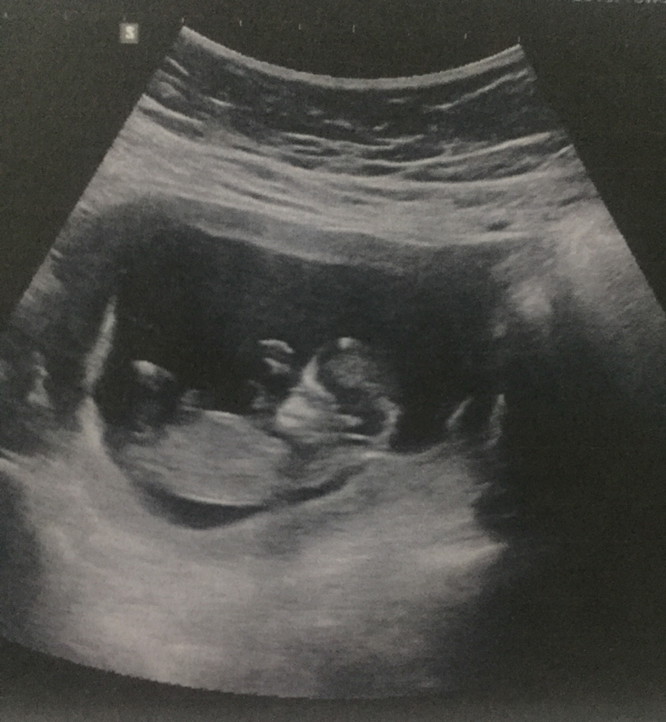

13 weeks

13w ค่ะ

13wค่ะ